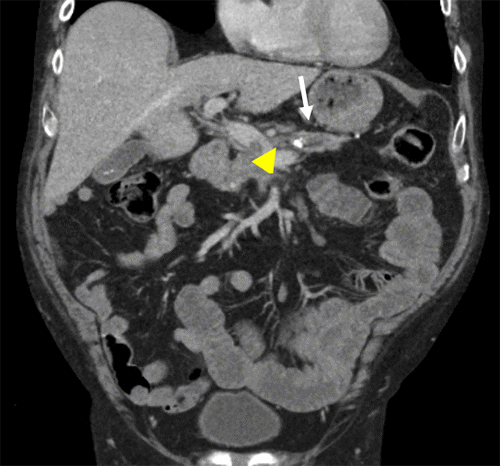

Figure 3. A) Axial and B) Coronal Images of Body and Tail of Pancreas. Published with Permission

Scans demonstrate a pancreatolith (white arrow) with upstream pancreatic duct dilation and focal pancreatic necrosis (yellow arrow). There is a small thrombus located in the adjacent SMV (arrowhead)

Scans demonstrate a pancreatolith (white arrow) with upstream pancreatic duct dilation and focal pancreatic necrosis (yellow arrow). There is a small thrombus located in the adjacent SMV (arrowhead).